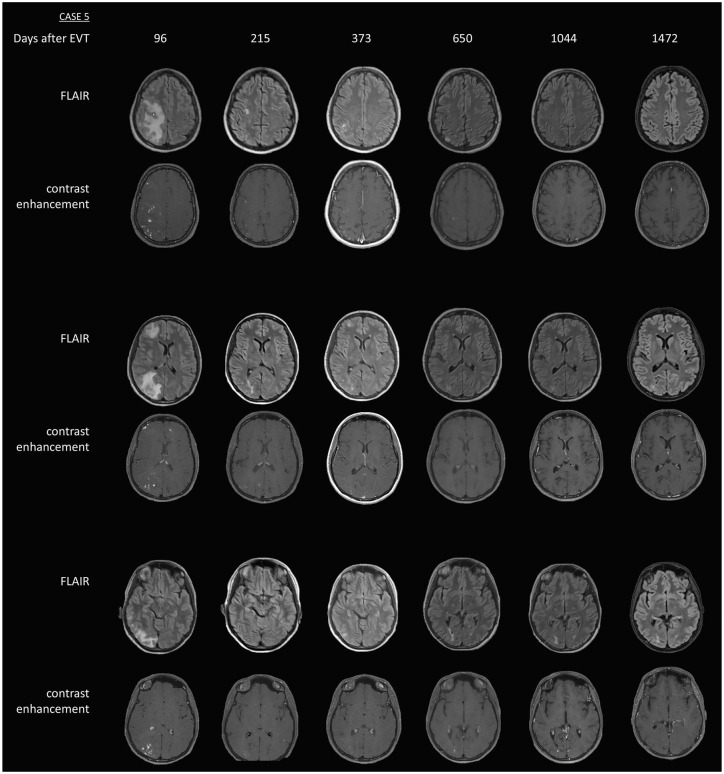

Objectives: In this study, we investigated the long-term follow-up of patients with NICE lesions, including magnetic resonance imaging (MRI) findings, clinical course, and treatment.

Results: We present the long-term follow-up of five patients already published and four additional cases. Nine female patients (mean age at diagnosis 50.67 ± 11.82 (± standard deviation, SD) years) were identified and analyzed with a mean follow-up of 1659.44 ± 1426.87 (SD) days, ranging from 328 to 5223 days (cumulative follow-up of 40.92 patient-years). In total, 112 MRIs were available for evaluation. Eight patients developed symptoms at a mean of 11 ± 13.41 (SD) days post-EVT, one patient remained asymptomatic. New NICE lesions during follow-up were detected in six patients, five patients developed new or increasing symptoms. All patients received glucocorticosteroids with variable duration, six patients required additional immunotherapies. At final follow-up, all patients had a favorable outcome (modified Rankin Scale 0-1), though residual symptoms persisted in four of them.

Conclusion: Hitherto, this study presents the longest follow-up period of patients developing NICE lesions after EVT. NICE lesions may have a highly variable course regarding radiological and clinical characteristics, with potential for both clinical and radiological recurrence years after initial presentation. While immunosuppressive therapy appears effective, optimal treatment regimens and duration have yet to be determined. Our findings underline the importance of regular clinical and MRI controls for individual patient care in this rare condition.